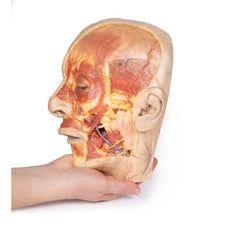

Viewed from the anterior aspect the face has been dissected to display some of the facial muscles around the mouth (buccinator [on the left], orbicularis oris and zygomaticus major). On the left side of the infratemporal fossa has been open to expose the medial and lateral pterygoids.

The lateral pterygoid is divided to show the mandibular division of the trigeminal nerve dividing into the lingual nerve and the inferior alveolar branch. Also on the left side the branches of the ophthalmic division of the trigeminal that supply the skin above the eyebrows and scalp (supraorbital [left only] and supratrochlear nerves [both sides]) are dissected. The submandibular gland is clearly visible below the mandible on both sides as are the facial arteries and veins as they course over the mandible.

Cranial Cavity: The left and right orbits have been opened to reveal the orbital nerves and vessels along with the eyes and optic nerves. The optic chiasm, optic tracts and the lateral geniculate bodies are retained thus showing a large part of the visual pathways. The brainstem is cut at the level of the superior colliculi on the left and slightly lower on the right. The olfactory tracts and bulbs are also demonstrated. The origins of many of the cranial nerves from the brainstem are clearly visible.

Viewed from the anterior aspect the face has been dissected to display some of the facial muscles around the mouth (buccinator [on the left], orbicularis oris and zygomaticus major). On the left side of the infratemporal fossa has been open to expose the medial and lateral pterygoids.

The lateral pterygoid is divided to show the mandibular division of the trigeminal nerve dividing into the lingual nerve and the inferior alveolar branch. Also on the left side the branches of the ophthalmic division of the trigeminal that supply the skin above the eyebrows and scalp (supraorbital [left only] and supratrochlear nerves [both sides]) are dissected. The submandibular gland is clearly visible below the mandible on both sides as are the facial arteries and veins as they course over the mandible.

Cranial Cavity: The left and right orbits have been opened to reveal the orbital nerves and vessels along with the eyes and optic nerves. The optic chiasm, optic tracts and the lateral geniculate bodies are retained thus showing a large part of the visual pathways. The brainstem is cut at the level of the superior colliculi on the left and slightly lower on the right. The olfactory tracts and bulbs are also demonstrated. The origins of many of the cranial nerves from the brainstem are clearly visible.